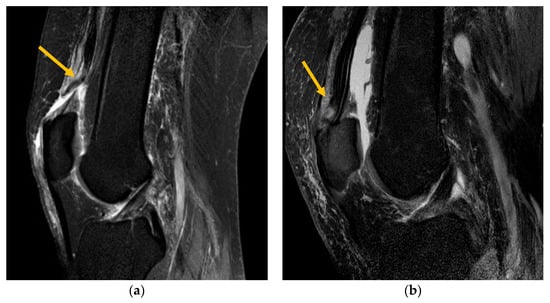

Altogether, the 33 evaluated MRI images showed 70 ruptures of subtendons (RF, VM, VL and VI). While 62.9% were complete ruptures, 37.1% partial ruptures could be identified (Figure 3). Complete rupture in the rectus femoris (30.0%) was the most common (Figure 4a), followed by complete rupture of the vastus medialis (15.7%). When combining the affected layers of the quadriceps tendon with the location, complete distal rupture of the RF subtendon was most common. Most patients (67%) showed multiple ruptures of subtendons compared with single tendon ruptures (33%).

Figure 4.

(a) T2-weighted sagittal MRI demonstrating complete QTR of the rectus femoris. (b) T2-weighted sagittal MRI demonstrating partial QTR of the rectus femoris subtendon.

For complete QTR, the mean retraction distance was 16.5 mm (range 4.0–36.0 mm). The most common associated pathology with QTR detected via MRI was pre-existing tendinosis (31.2%). This was more frequent in complete ruptures (33.3%) than in partial ruptures (22.2%).